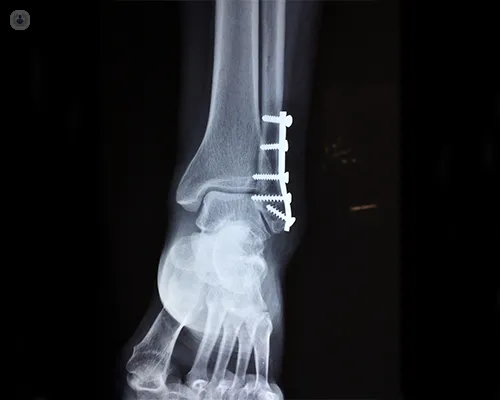

2. Internal Fixation:

• Using plates, screws, or intramedullary nails.

• Provides stability for complex but clean fractures.

3. Definitive Fixation: External fixator (Ilizarov/hexapod) or internal plates/nails.

4. Bone Healing: Regular monitoring with X-rays.